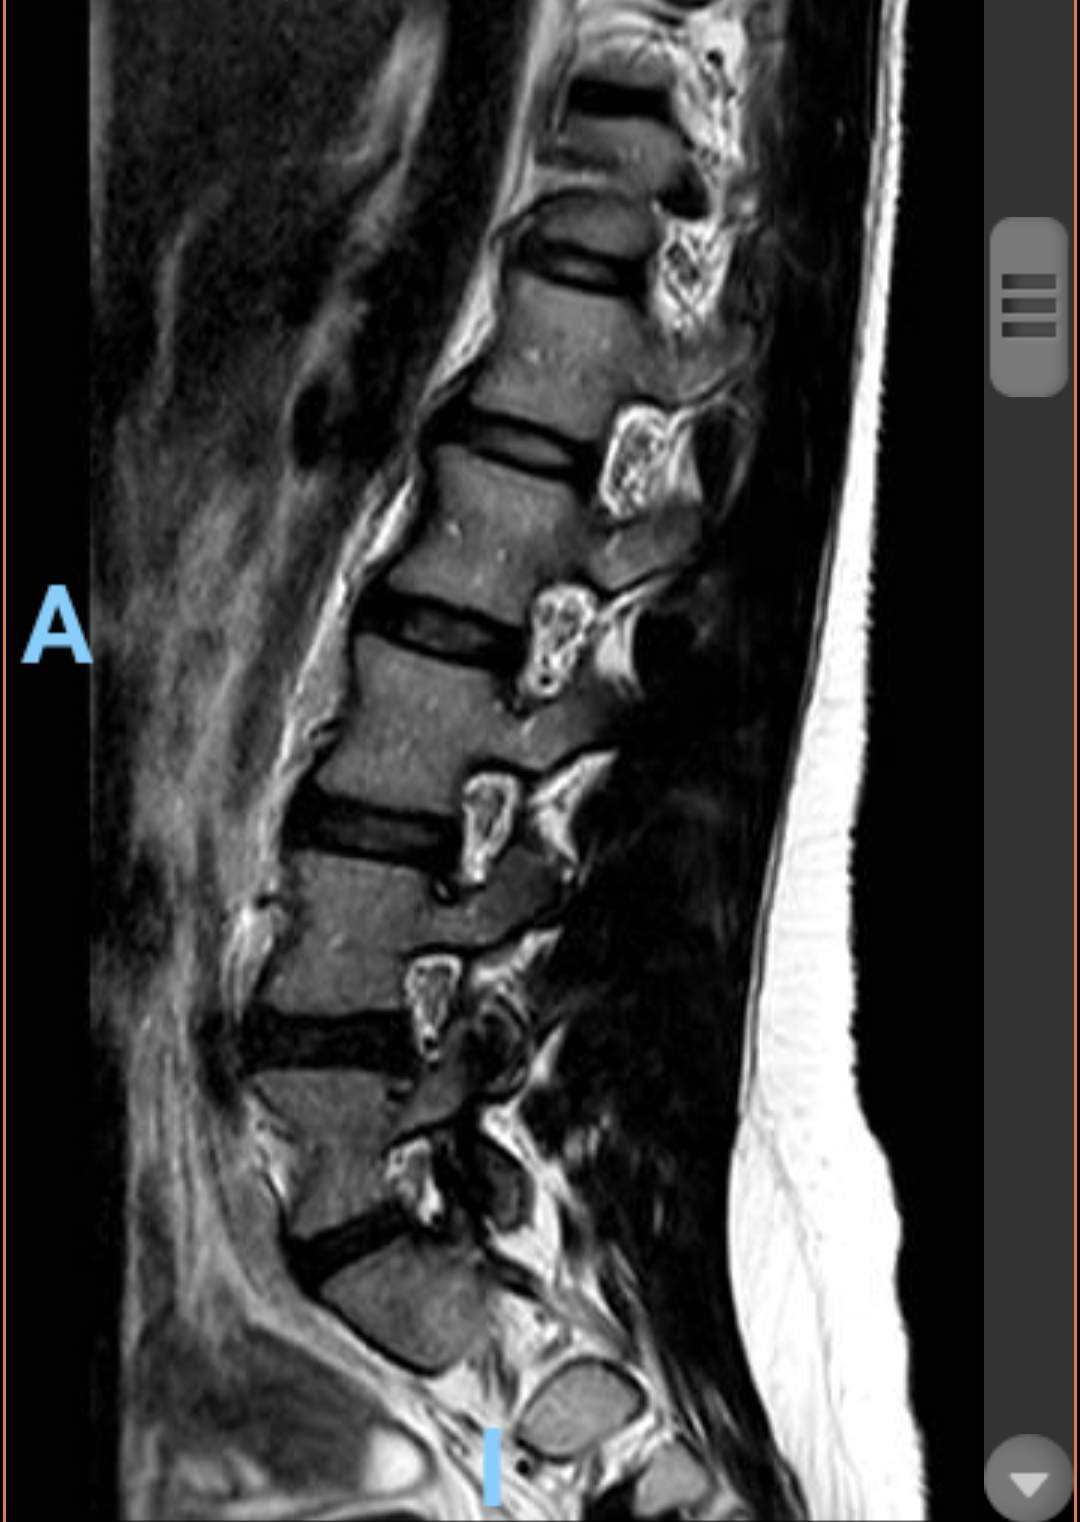

Ventrolisthesis und Bandscheibenvorfall in LWS

MRT Bilder LWS erste Einschätzung?

Wer kann mir etwas zu meiner LWS sagen? (Bandscheibenvorfall, MRT Befund)

Wer kann mir diese MRT Aufnahmen der LWS auswerten ? (Wirbelsäule, Befund)